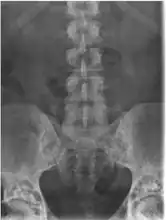

Diagnostic methodX-ray, ultrasound[4]

It is a genetic disorder associated with LEMD3.[6][7] It is inherited in an autosomal dominant manner.[2] In a very few, X-rays may show several areas of compact bone.[1] Conditions that may appear similar include tuberous sclerosis, pseudoxanthoma elasticum, neurofibroma, and lipoma, among others.[1]

The diagnosis of this condition can be ascertained via several techniques one such method is genetic testing, as well as:[3][4]

• X-ray